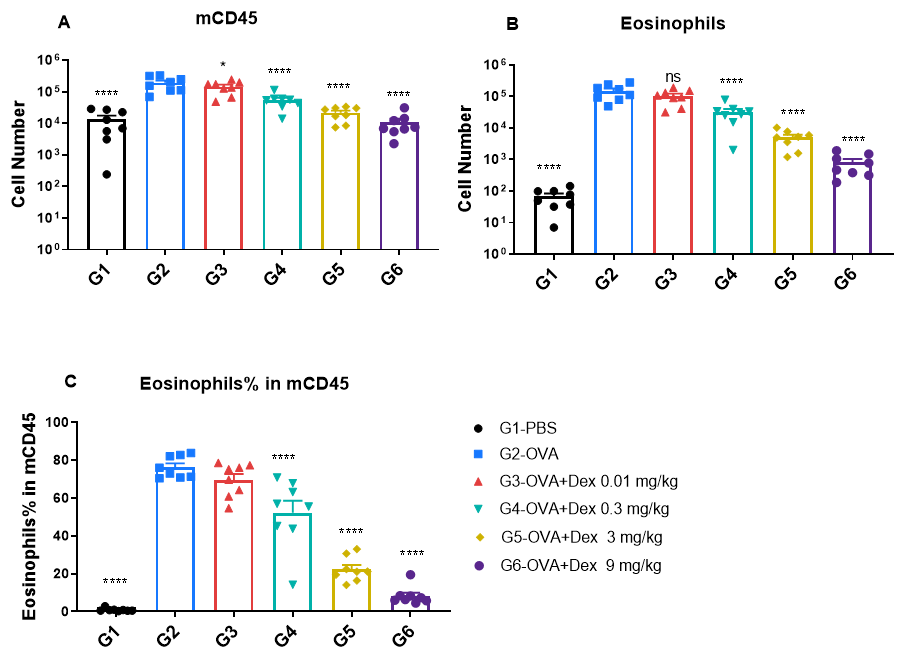

Quantification of immune cells in bronchoalveolar lavage fluid (BALF) of OVA-induced asthmatic BALB/c mice. Asthma was induced in wild-type BALB/c mice by ovalbumin (OVA) sensitization and challenge. (A) Total CD45⁺ leukocyte count in BALF; (B) eosinophil count in BALF; and (C) frequency of eosinophils among CD45⁺ cells. Mice in the OVA-induced asthma group (G2) exhibited significantly elevated total leukocytes and eosinophils compared to PBS-treated controls (G1), confirming successful model induction. Dexamethasone treatment significantly reduced CD45⁺ cell counts and eosinophil levels in asthmatic mice relative to the untreated G2 group.